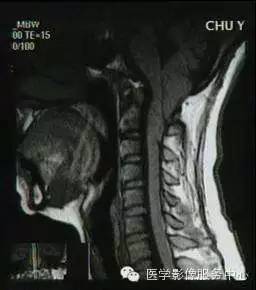

Chiari畸形I型 (图源见水印)

Chiari畸形II型(CM-II):通常与脊髓脊膜膨出(一种神经管闭合不全的先天性畸形)相关,常见于婴儿。几乎所有患者均合并脊髓空洞和脑积水。